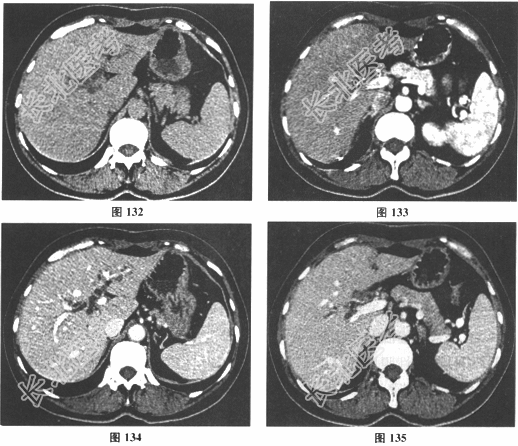

- [材料题] 女性,55岁。主诉腹腔镜胆囊切除术后3个月,皮肤巩膜黄染伴瘙痒20余天入院。3个月前在当地医院行LC术,术后因"胆漏"再次手术,发现"胆管小破口",予"缝合胆管破口+T形管引流术",术后1.5个月复查肝功正常后拔出T形管。拔管后2周出现皮肤巩膜黄染。无发热、寒战,有恶心、呕吐,间断有上腹部疼痛,无腹泻,无大便颜色变浅。当地医院MRI检查提示"肝内外胆管扩张"。病来无明显体重减轻。有高血压病史6年,平素口服苯磺酸氨氯地平片控制血压,血压时有波动。入院后化验:Hb129g/L,WBC5.44×109/L,N0.67,PLT362×109/L,PT11.3s,ATPP39.1s,PTA149%,INR0.82,Fib4.58;ALT419.6U/ml,AST330.5U/ml,Alb38.5g/L,TB141.9μmol/L,DB111.5μmol/L,TBA261.2μmol/L,AKP780.3U/L,GGT1627U/L;AFP4.36ng/ml,CEA0.37μg/ml,CA19-918.5U/ml;乙肝(-)。CT和MRCP检查结果见图。

- 多项选择题1.请问该患者的临床诊断为( )

- 多项选择题2.该患者胆管损伤的Bismuth分型为( )